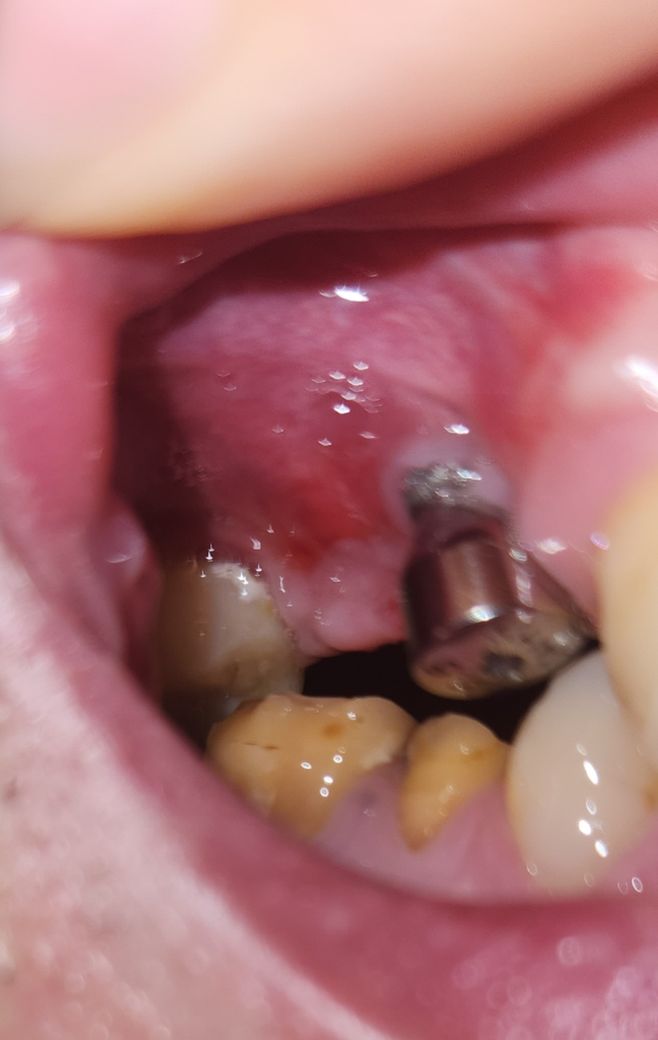

잇몸에는 붉은색을 띠는 부분이 있습니다.

임플란트 주변에도 경미한 염증이 보이는듯해 보여요.

사진으로만 판단하기에는 염증의 여부를 정확하게 알기 어렵습니다.